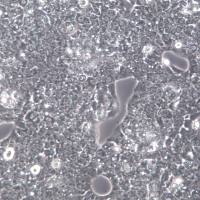

Hela细胞、Hela、Hela

HepG2细胞

CHO、中国仓鼠卵巢细胞;CHO、CHO细胞

技术资料/正文

细胞冻存复苏